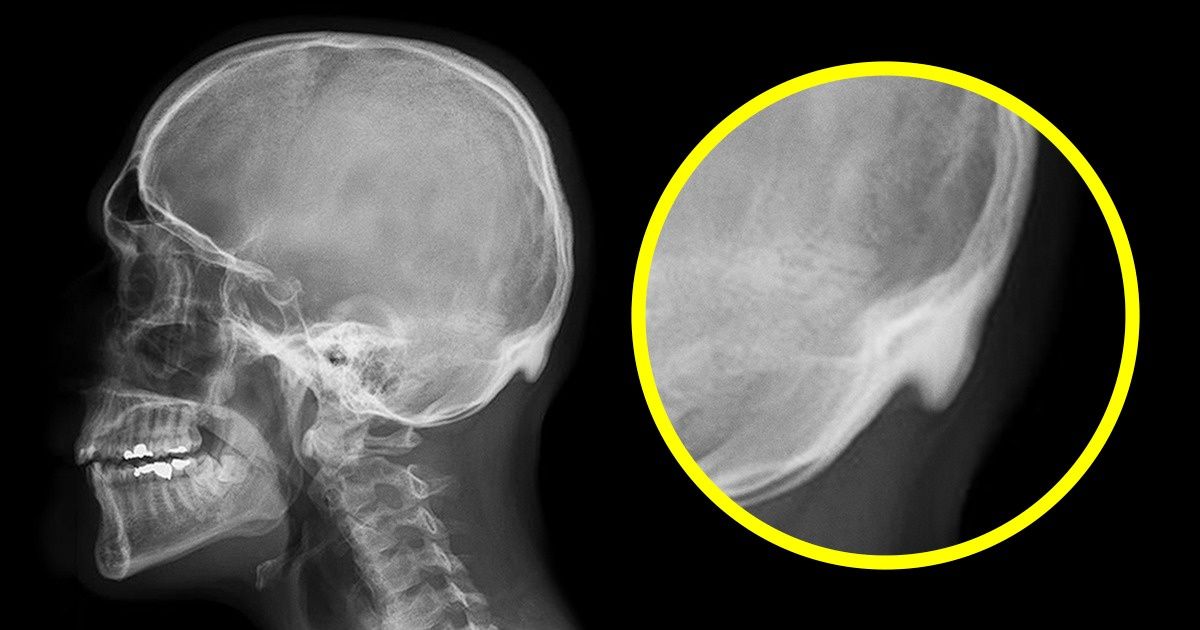

218 personnes, âgées de 18 à 30 ans, ont participé à l’étude. Sur leurs radiographies, le docteur David Shahar a trouvé une bosse osseuse sur la nuque de 41% des sujets. Les scientifiques ont estimé que cette bosse était considérée de taille importante à partir de 10 mm. Chez 10% des sujets de l’étude, cette bosse inexplicable dépassait plus de 20 mm et sa longueur maximale était de 35,7 mm chez les hommes et de 25,5 mm chez les femmes.

Pour la deuxième étude, les scientifiques ont augmenté le nombre de participants, cette fois âgés de 18 à 86 ans. Les résultats ont montré que la bosse en question était plus fréquente chez les jeunes. Cette observation a permis au docteur Shahar et son collègue Marc Sayers d’émettre l’hypothèse selon laquelle cette lésion des os serait causée par des troubles de la posture. À cause de son inclinaison forcée vers l’avant, le poids de la tête se répartit différemment et cela crée une pression à l’endroit où les muscles relient la tête et le cou. Par conséquent, cela provoque des changements dans les os et les ligaments. Selon les chercheurs, la bosse en elle-même ne serait pas dangereuse, mais c’est la déformation de la colonne vertébrale qui risque de causer d’autres troubles dans le corps humain.